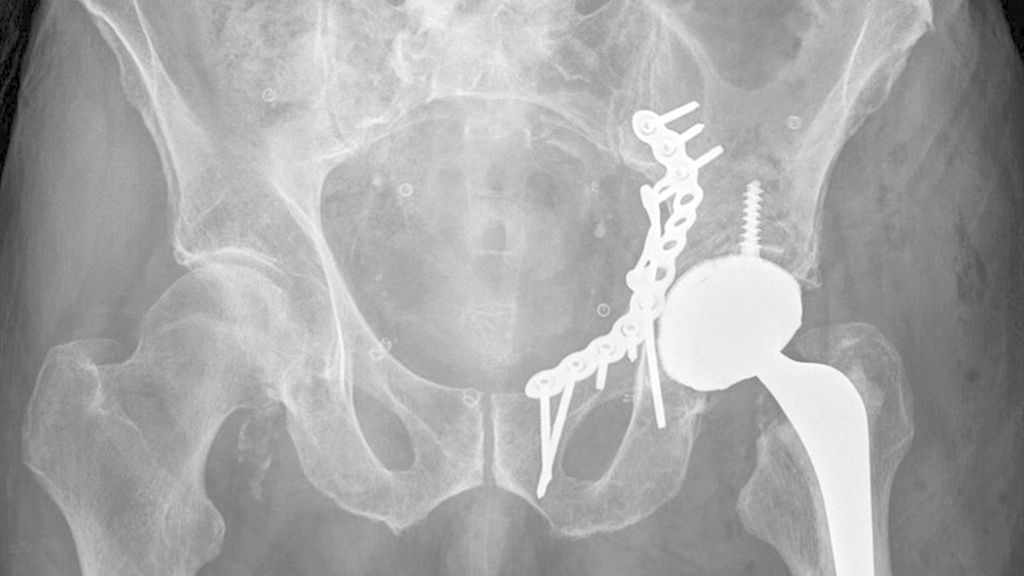

Die Mehrheit der Herausforderungen bei der Behandlung der Fragilitätsfraktur des Acetabulums überschneidet sich mit denen bei Beckenringfraktur. Ebenso wenig überraschend treten auch auf der anderen Seite des Hüftgelenkes ähnliche Komplikationen und eine Reduktion der Lebenserwartung wie bei hüftnahen Oberschenkelfrakturen auf. Im Unterschied zu den FFP gilt dieselbe Klassifikation für Hochrasanz- und Niedrigenergietraumata des Acetabulums nach Judet und Letournel. Der große Unterschied besteht jedoch in der Häufigkeitsverteilung. Aufgrund der meist einfachen Stürze mit Gewalteinwirkung über den Trochanter major betreffen die Fragilitätsfrakturen des Acetabulums meist den vorderen Pfeiler und die quadrilaterale Fläche. Entsprechend sind dislozierte Frakturen eine Domäne der offenen Operationsverfahren und der Hüftendoprothetik. Der Stellenwert der minimalinvasiven Stabilisierung nicht dislozierter Acetabulumfrakturen und der Stabilisierungen in Fehlstellung ist wissenschaftlich nicht geklärt. Jedoch gibt es zunehmende Literatur über das sogenannte „fix and replace“, bei dem eine Osteosynthese eines Pfeilers mit einer primären Totalendoprothese in einer Operation kombiniert wird (Abb. 2).

Abb. 2: „Fix and replace“ mit Osteosynthese und Hüfttotalendoprothese in der selben Operation bei geriatrischer Acetabulumfraktur mit Impressionsfraktur des Doms

Bisher konnten dabei keine erhöhten Komplikationsraten gegenüber der konventionellen Osteosynthese festgestellt werden. Gleichzeitig besteht aber der Vorteil der Vollbelastbarkeit, des Einsatzes einer konventionellen Pfanne und der in der Orthogeriatrie erwünschten „one-shot surgery“ (nur eine Operation statt einer potenziellen zweiten Operation bei Versagen der Osteosynthese und sekundärer Prothese). Bei ca. 30% der geriatrischen Acetabulum-Osteosynthesen in der Literatur erfolgte eine Revision mittels Prothese. Risikofaktoren für die Notwendigkeit einer sekundären Hüfttotalendoprothese nach Osteosynthese sind: höheres Alter, Impressionsfrakturen des Doms und Hüftkopfes, Medialisierung des Hüftkopfes („zentrale Hüftluxation“), nichtanatomische Reposition (häufig durch späte Versorgung nach konservativem Therapieversuch oder längerer Operationsvorbereitung bei Multimorbidität).

Die „Fix and replace“-Behandlungsoption ist gerade für Zwei-Pfeiler-Frakturen interessant, da bei dieser häufigen geriatrischen Frakturform aufgrund der vorliegenden sakroiliakalgelenksnahen Beckendiskontinuität selbst durch gängige Revisionspfannen nicht immer eine Belastungsstabilität erreicht werden kann (Abb. 3).

Im Gegenzug dazu wird in der Literatur auch eine minimalinvasive offene Osteosynthese beschrieben, wobei man auf ausgedehnte Repositionsmanöver mit dem damit verbundenen Blutverlust verzichtet. Dadurch werden zum Teil verbliebene Fehlstellungen akzeptiert bzw. wird durch postoperative Mobilisierung eine sekundäre Dislokation in Kauf genommen, um eine postoperative Vollbelastung zu ermöglichen. Eine entsprechende Operationstechnik über einen Stoppa-Zugang und mit Plattendesign mit Abstützung der quadrilateralen Fläche wurde durch Culemann 2023 anschaulich beschrieben.12 Bei geschwächter Knochenqualität ist neben dem Plattendesign mit medialer Abstützung an der quadrilateralen Fläche auch das Augenmerk auf eine stabile Verankerung zu legen. Die infraacetabuläre hintere Pfeiler-Schraube, welche meist um die 100mm Länge aufweist, ist hierbei sehr empfehlenswert (Abb. 2 und Culemann 202312).